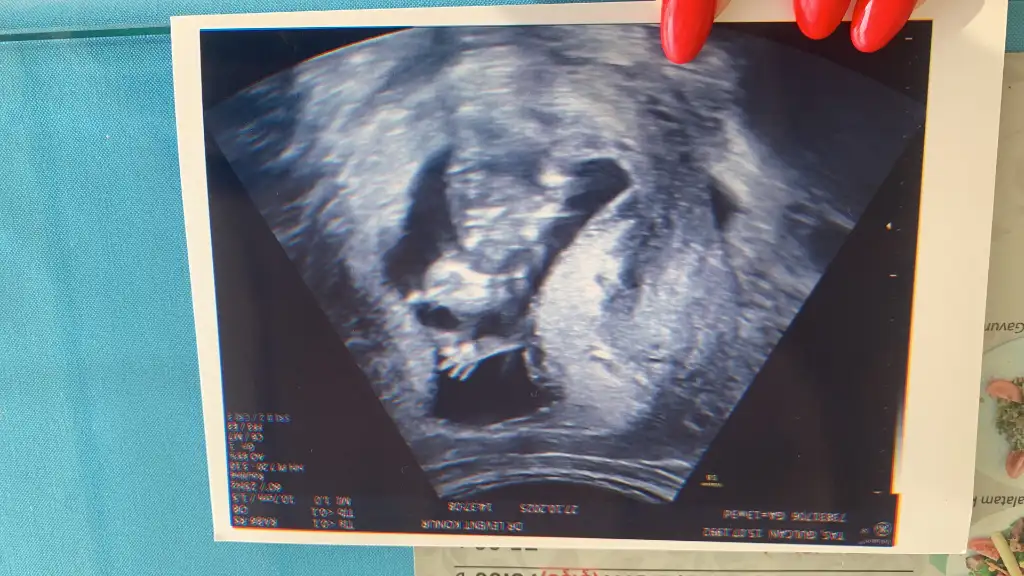

Kız cinsiyetimiz

13+3 teyiz

Çok net belli etti organı oluşmuş

Kız bebiş geliyor 🌸